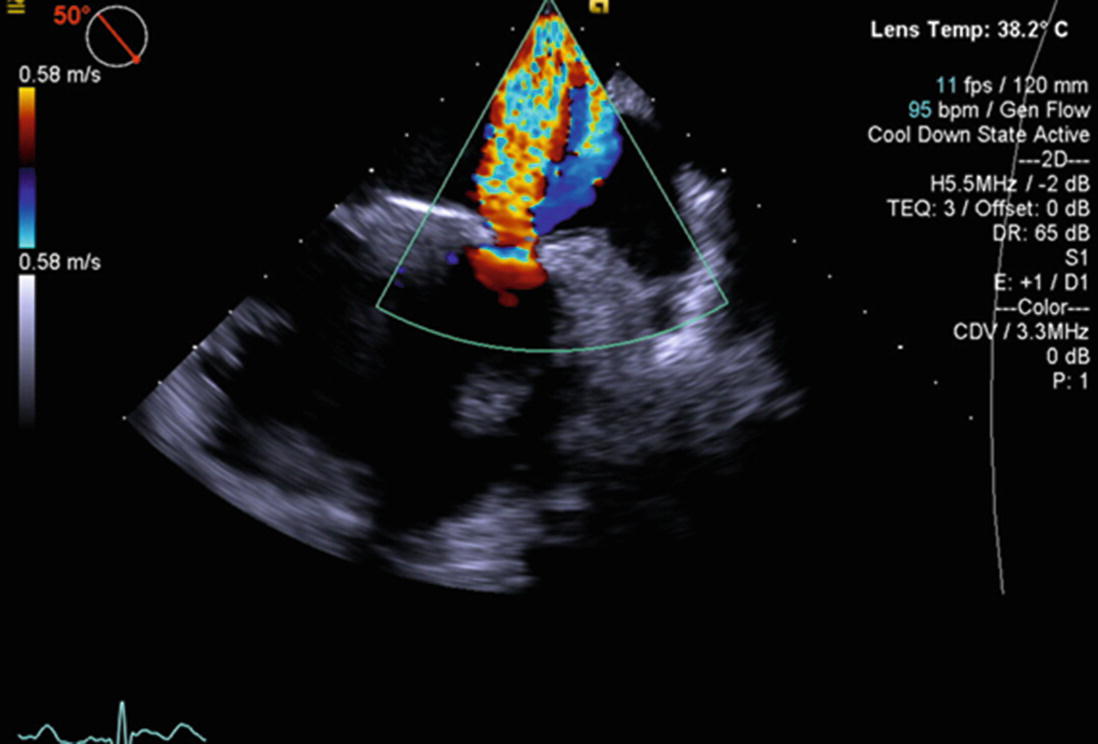

Steps In Paravalvular Leak Closure Echographic Perspective A 3d Echo Download Scientific Diagram Percutaneous closure of paravalvular leak after transcatheter valve implantation in mitral annular calcification by guillaume leurent et al.